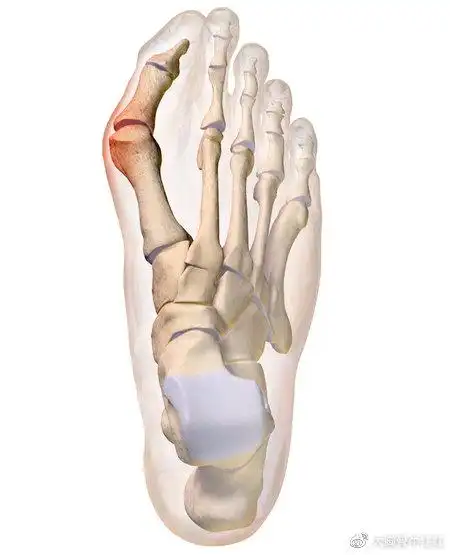

大脚骨病的微创手术

如何正确矫正大脚骨超微创真的这么好吗

拇外翻大脚骨手术矫治术